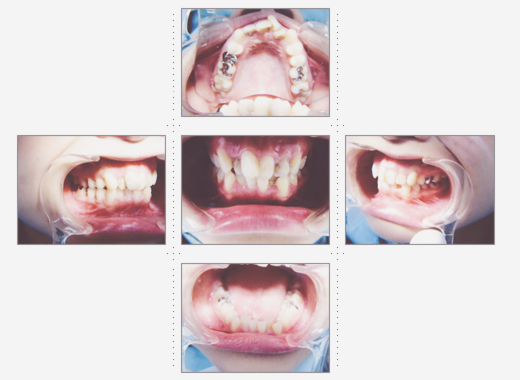

症例3

主婦 56才 女性

入れ歯が合わず食事がうまくできないので、食べれるようになりたい。人前で堂々と話をしたり、笑ったりしたい、というご希望でした。

術後は、よく噛めるようになり、栄養のバランスがよくなり、肌にツヤとハリが出て、エステに通うより効果がありました、と喜んでいただきました。